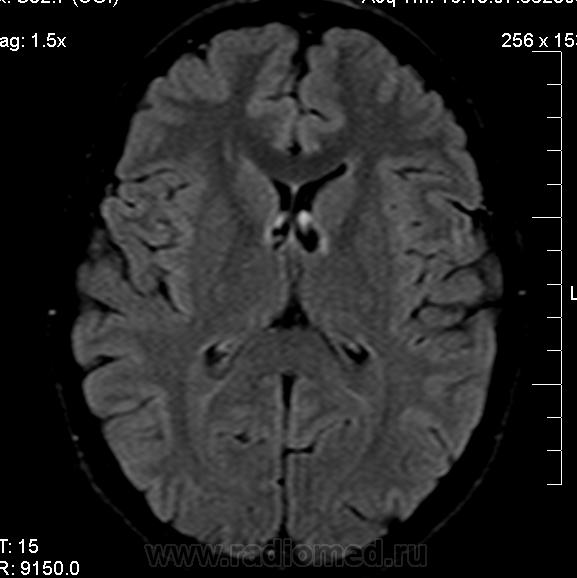

Можно ли  трактовать участок повышенного МР-сигнала по Т2 в правой лобной доле как участок перивентрикулярного глиоза?

1) господа МРТшники, если это расширенное вирхов-робиновское пространство, как вы объясните тот факт, что в TIRM последовательности сигнал от данного участка высокий?

2) данная находка (единичный мелкий дисциркуляторный очаг) имеет мало практической ценности. не описали бы - ничего страшного. такие перивентрикулярные изменения бывают у очень многих людей и тяготеют к норме для тех, кто старше 40 лет.

3) термин "глиоз" - гистологический, и применять его в лучевой диагностике некорректно, ИМХО.  в дисциркуляторных очагах помимо глиоза находят и другие изменения.